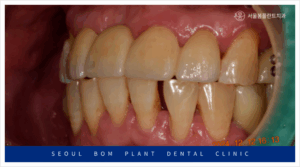

양측 위아래 어금니의

임플란트 보철물이 마무리되고 나서

앞니 심미보철치료를 진행하였는데요.

앞니는 심미성이 중요한

부위이다 보니 치아를 다듬기 전

환자분과 함께 색상과 모양을

꼼꼼하게 확인하는 작업을 거쳤으며

보철물 수복에

필요한 만큼의 양만 삭제하여

신경치료 없이 진행을 하였습니다.

앞니도 어금니와 마찬가지로

심미성이 높은 지르코니아

보철물로 수복해 드리면서

모든 치료를 마무리해 드렸는데요.